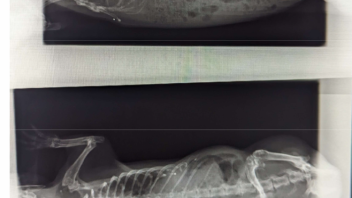

Dies zeigt an, dass etwas nicht stimmt und dass es sich hierbei um ein krankes Schweinchen handelt, auch wenn der Tierarzt nichts findet.

Da ist etwas im Argen, was es zu entdecken gibt.

Dein Tierarzt sollte so lange mit dir zusammen nach der Ursache suchen, bis sie gefunden ist.